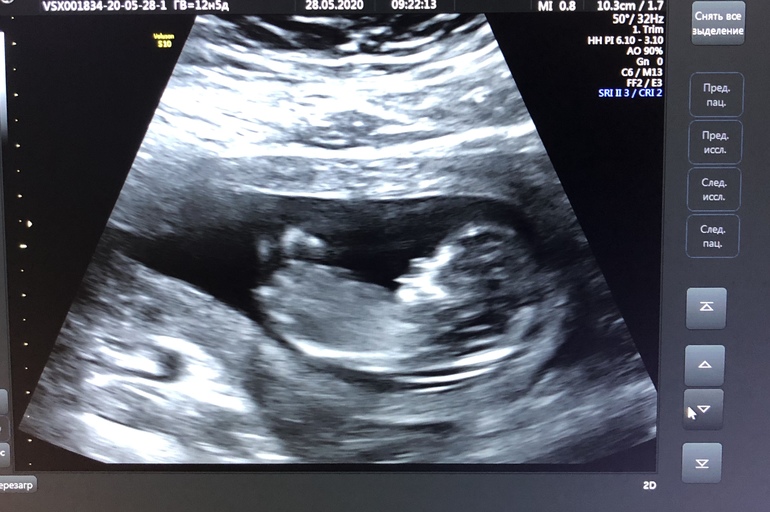

12 1 узи

12 1 узи 118 фото